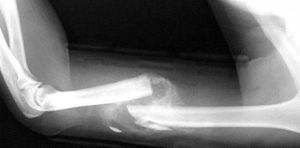

Was würde Robert Franz nach einem Knochenbruch tun?

In diesem Beitrag geht es um das schmerzhafte Thema Knochenbrüche und wie man die Knochen [...]